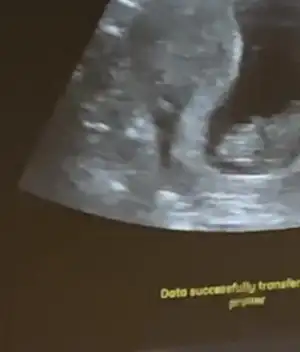

Erkek görünüyor başka USG olursa paylaşınBanada tahminde bulunur musunuz ? ben hiç bir şey anlamadım

11+3 burda

11+3 burda

Kız gibi sanki başka USG varsa paylaşınBana da yorum yapabilirsiniz 12+4

Başka yok malesef doktor hafif çıkıntısı var ama erken dedi teşekkürlerKız gibi sanki başka USG varsa paylaşın

Şuan başka usg yok. Hayırlısı bakalım 2 erkek anası mı olacağımErkek görünüyor başka USG olursa paylaşın

Merhabaa bana da tahmin yaparmisinizErkek görünüyor başka USG olursa paylaşın

Erkek sanki Emi olamadim çok karanlık tekrar USG paylasinIkra meyra bana da tahminde bulunur musun rica etsem? Dr herhangi birşey söylemedi, belli değil dedi.. 12+2

Daha aydınlık sanirim şimdiErkek sanki Emi olamadim çok karanlık tekrar USG paylasin

Kız görünüyor